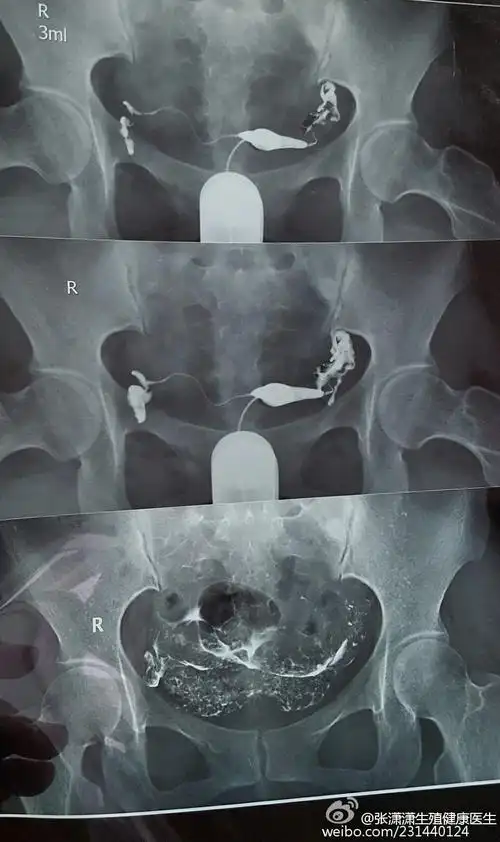

多囊卵巢,一侧输卵管不通,宝妈准备试管却怀孕了,心态很重要

学会自己看输卵管造影片

麻烦相关专业的医生帮我看下,我这个输卵管造影的图片,是哪一段堵塞